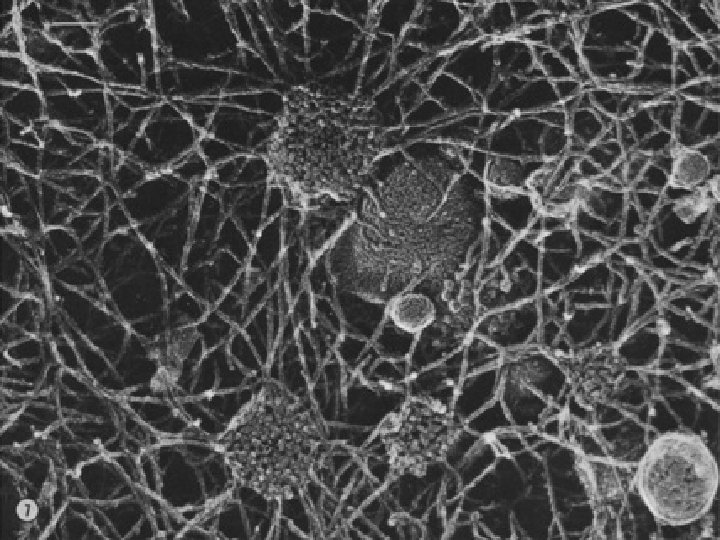

Detail plicních sklípků alveol

Ciliární karcinom - histologie